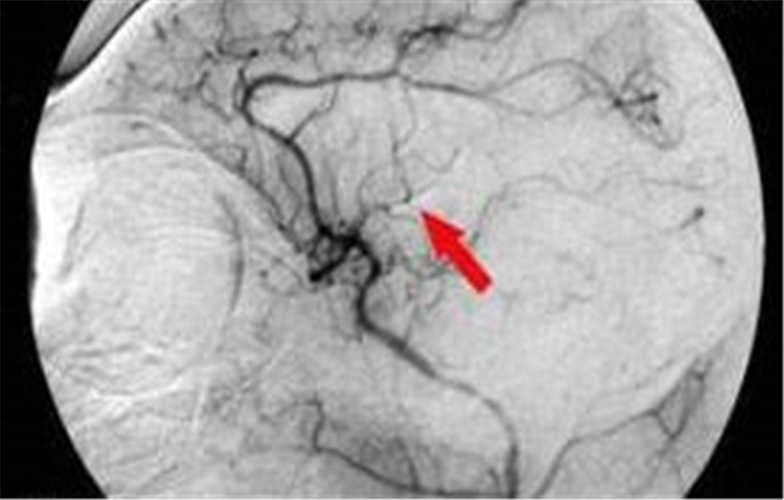

腦供血不足造影